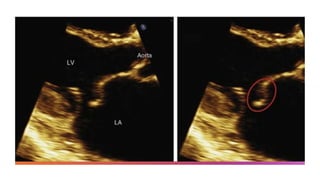

• The most common cause of primary MR in developed countries is MV prolapse or flail

(Carpentier type II)

• Prolapse is defined as leaflet billowing by more than 2 mm above the annular “plane” during

systole.

• assessment is typically made in the parasternal long axis view, which displays the highest

points of the saddle-shaped annulus.

• The diagnosis of prolapse should not be made exclusively from the apical four-chamber view,

which shows lower (more apical) points on the annulus.

• MV prolapse spans a spectrum from minimum prolapse of the leaflets into the left atrium to

diffuse leaflet thickening and redundancy.

• Flail leaflet is part of the MV prolapse spectrum and is defined as occurring when the leaflet

becomes everted and loses its normal convex shape with the leaflet tip seen within the left

atrium.

• Flail leaflet is caused by disruption of the primary (marginal) chordae such that effective

coaptation is no longer present.